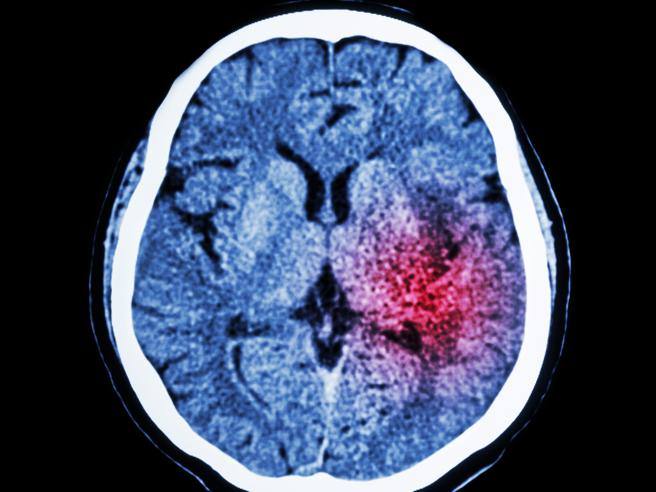

La démence et les pertes de mémoire qui affectent la vie quotidienne ne sont pas typiques du vieillissement normal et méritent d’être portées à l’attention d’un médecin. En général, le symptôme le plus précoce et le plus évident de la maladie d’Alzheimer est le symptôme significatif perte de mémoire qui se manifeste, surtout au début, avec des difficultés à se souvenir des événements récents. Ils peuvent alors apparaître troubles de la parole etDifficulté à nommer les objets, appauvrissement de la parole jusqu’à la perte de l’expression correcte des pensées. Un autre symptôme courant désorientation spatiale et temporelle. Ils sont aussi fréquents altérations de la personnalité, méfiance à l’égard des personnes accusées de vol et changements d’humeur du taureau. Certaines difficultés sont en fait à considérer comme un changement typique lié à l’âge tandis que d’autres comportements pourraient représenter des sonnettes d’alarme qu’il ne faut pas sous-estimer. Voici comment vous orienter grâce aux conseils du Centre IRCCS Alzheimer Centro San Giovanni di Dio Fatebenefratelli de Brescia